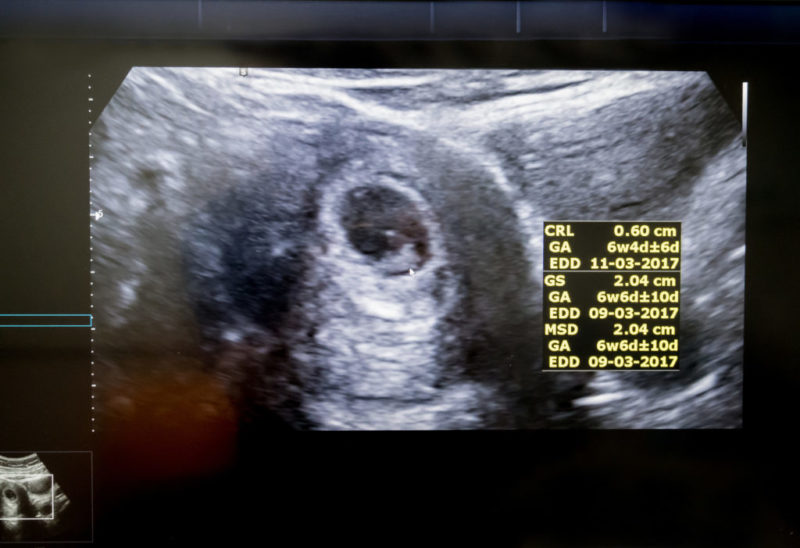

Primera Ecografía de embarazo tras los Tratamientos de Fertilización in Vitro

Dr. Joaquín Llácer, Co-Director Médico. Medicina Reproductiva del Instituto Bernabeu. Confirmación de embarazo tras FIV y Donación de óvulos (Ovodonación). La primera ecografía en la que podemos apreciar el embarazo, constituye uno de los momentos más emotivos en la vida de todos los padres. Esta situación es especialmente relevante en las pacientes sometidas a tratamientos de reproducción asistida, en estas parejas, tras comunicarles el resultado […]